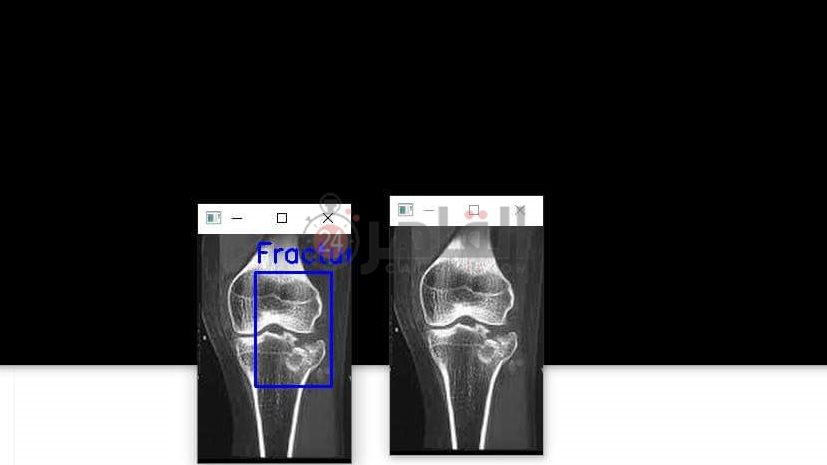

وتابع أحمد في حديثه لـ القاهرة 24، أن عدد الطلاب المشاركين في تصميم المشروع وصل عددهم لـ28 طالبًا وطالبة، لافتًا إلى أن الروبوت أيضًا يقوم بتحديد الكسور بدقه لدى المرضى ويستطيع إخراج تقرير مفصل عن حالة الكسر وتحديد مكانه بكل سهولة.